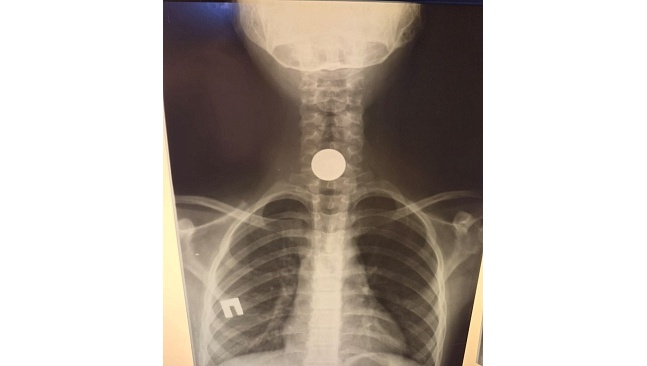

В стационар Балаковской городской клинической больницы Саратовской области поступила девятилетняя девочка.

По словам ребёнка, когда она играла на улице, чтобы не потерять 5-рублёвую монетку, положила её в рот под язык.

В какой-то момент девочка поняла, что она её проглотила.

Родители обратились за медицинской помощью, сообщает телеканал «Саратов 24».

В больнице под общим наркозом монетку извлекли из пищевода ребёнка.

По словам медиков, обращение к врачам было своевременным, так как инородный предмет застрял на входе в пищевод. В таких случаях медлить нельзя, последствия могут быть необратимыми.

фото: Балаковская городская клиническая больница